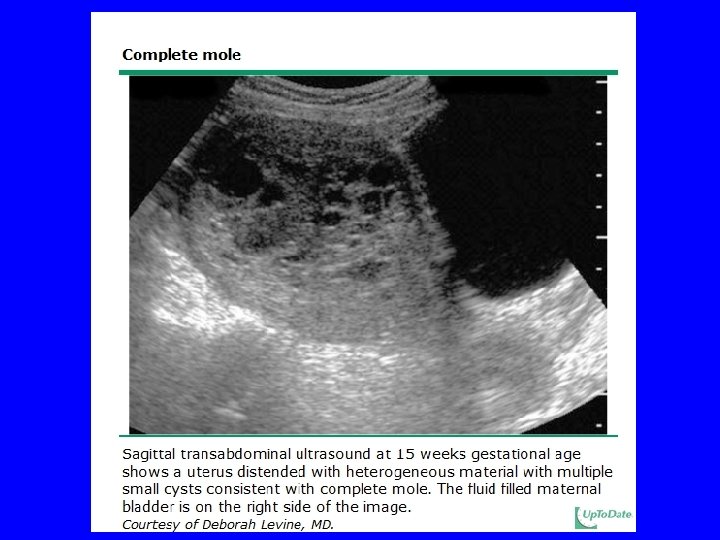

Hydatidiform Mole Clinical Manifestations: • Vaginal bleeding/anemia • Enlarged uterus (size > dates) • Pelvic pain • Theca lutein cysts • Hyperemesis gravidarum • Hyperthyroidism • Preeclampsia <20 weeks gestation • Vaginal passage of hydropic vesicles

Hydatidiform Mole Treatment • Evaluate for coexisting conditions: - History and physical - CBC, coagulation profile, serum chemistry - thyroid function - blood type and crossmatch - chest radiography - pelvic ultrasonography • Evacuation of mole - Suction curettage - Hysterectomy if completed childbearing • If Rh negative, give rhogham